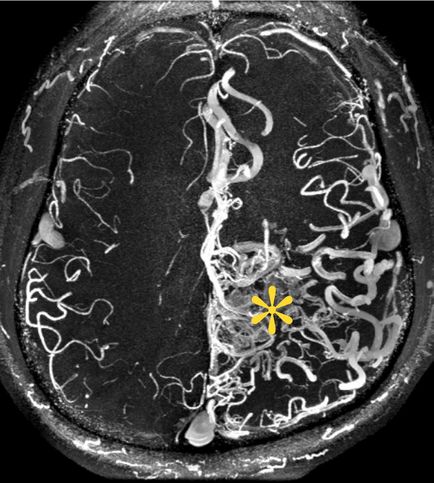

Minden arteriovenosus rendellenességek (AVM) egy tipikus szerkezete:

1.2 - kapott artéria (terminál tranzit és típusa)

3 - a kusza módosított hajók (kernel)

4 - ürítési Bécs

Diagnózis arteriovenosus rendellenességek, mint például, amikor subarahnoialnom vérzés vagy agyi tumor Moz (típusától függően az áramlás).